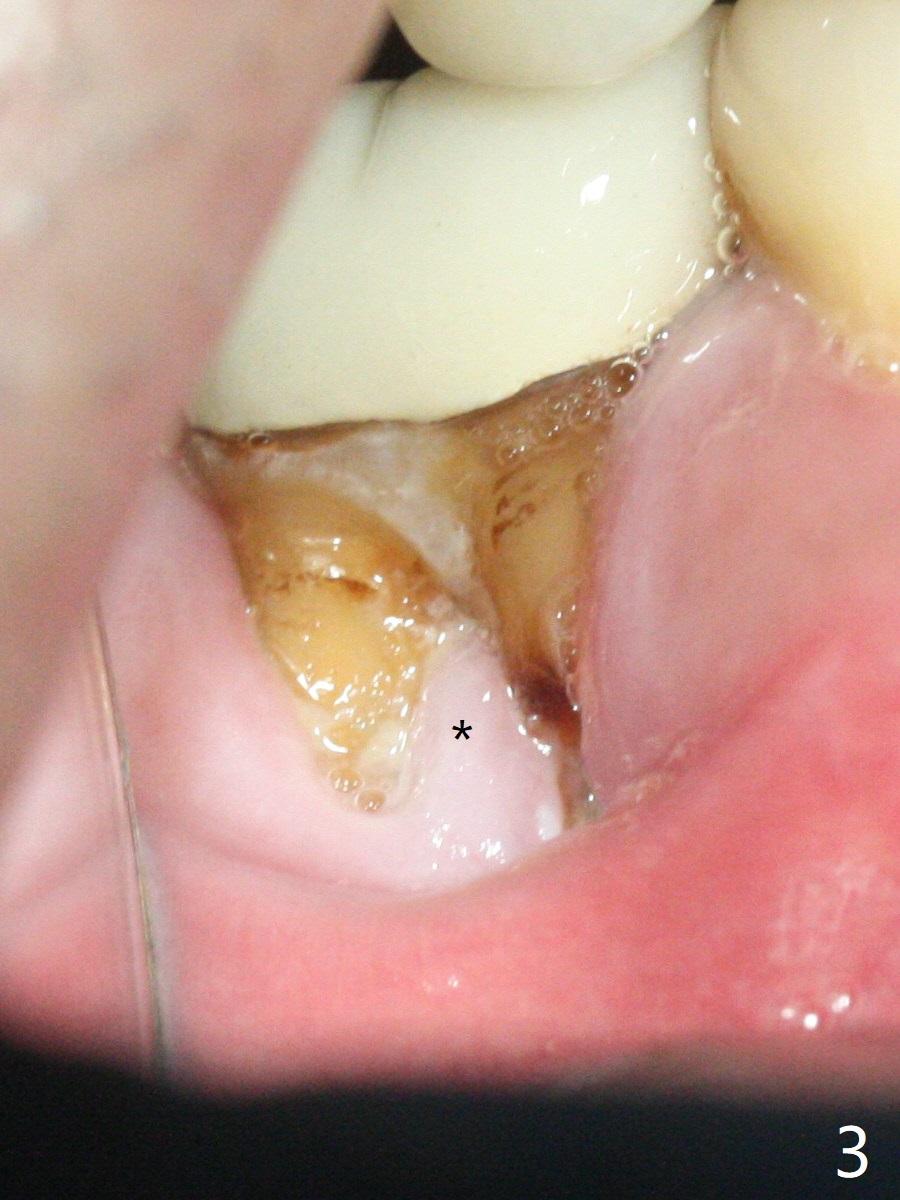

A 47-year-old man has poor dentition. The tooth #31 needs RCT, while #30 has severe PARL, especially mesial (Fig.1 M). The buccal roots are exposed (Fig.2). Between the exposed roots is the septal gingiva, which will be saved for buccal soft tissue repair (Fig.3 *). The septal gingiva will keep in place (not to be transferred) so that the recession will disappear by epithelial regrowth from the nearby gingiva (Fig.3' arrows) over the bone graft and PRF. The provisional should be fabricated to cover the soft tissue defect (Fig.3'' yellow area). In fact the mesial root fractures (Fig.4 ^), as related to the severe bony defect. There seems to be enough lingual bone to hold a 4x13 mm implant (Fig.5 green). Sticky bone (Fig.6 red circles) and PRF (blue) are to be used to repair the hard and soft tissue defects following an immediate provisional (Fig.5,6 yellow outline). Extra layer of acrylic (Fig.6 orange) will be used to cover the PRF buccally. The base of the buccal plate is thick (Fig.6 *); mesial portion appears to be denser (Fig.7 black *) than the distal one (white *). Decortication will be done if hemorrhage is insufficient. Fig.8 is a coronal section of the socket (B: buccal). Extraction (Fig.9 black area) will most likely result in a knife edge ridge. Extraction with bone graft may not fare better, as it is easy to lose the graft considering missing buccal hard and soft tissues.